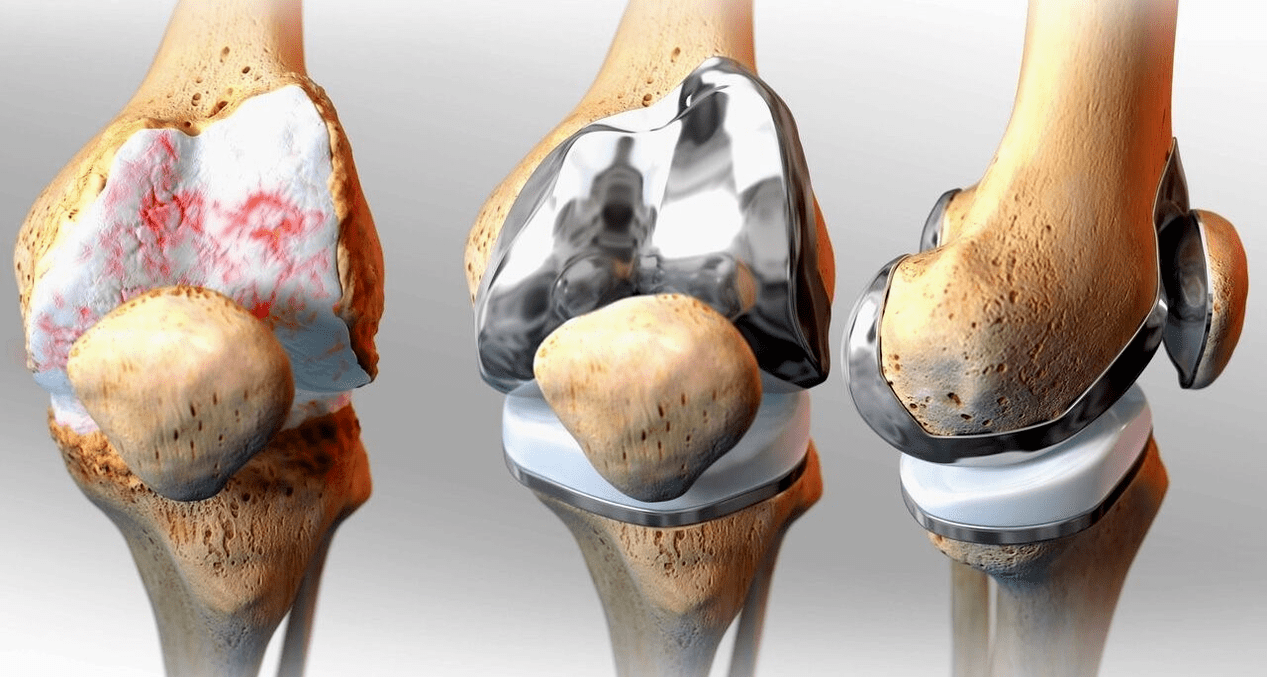

Chirurgische behandeling en endoprotheses

Endoprothesevervanging is een gebruikelijke en effectieve chirurgische methode voor de behandeling van ernstige gonartrose, waardoor u de mobiliteit van uw ledematen kunt behouden en vervolgens een volledig leven kunt leiden. Het gaat om een hightech operatie van ongeveer anderhalf uur. In de postoperatieve periode zijn langdurige revalidatie en ontwikkeling van het gewricht noodzakelijk. Na 25-30 jaar, wanneer het kunstgewricht versleten is, moet het opnieuw vervangen worden.